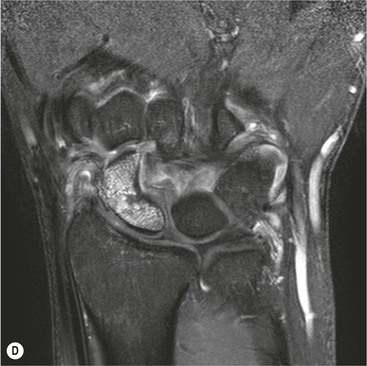

Abnormal communication between the radiocarpal and midcarpal joints may be seen on arthrography (Fig. 46-28), which is usually combined with MRI or CT16 (Figs. 46-29 and 46-30). However, direct visualisation of the ligaments is possible with conventional MRI. The most important features to describe that help determine management include the following:

The TFC is composed of fibrocartilage and is normally low SI on all MRI pulse sequences (Fig. 46-31). Tears of the TFC complex may present as ulnar-sided wrist pain. They occur as either a degenerative phenomenon or as an acute injury. Degenerative tears frequently result in central perforation of the TFC (Fig. 46-32), and are associated with positive ulnar variance (long ulna). This in turn may lead to ulnar abutment on the triquetrum, which is another cause of ulnar-sided wrist pain.

Traumatic TFC tears often affect the ulnar attachments and are associated with ulnar styloid fractures (Fig. 46-33). These injuries may also involve the dorsal and volar radioulnar ligaments and can lead to DRUJ instability.